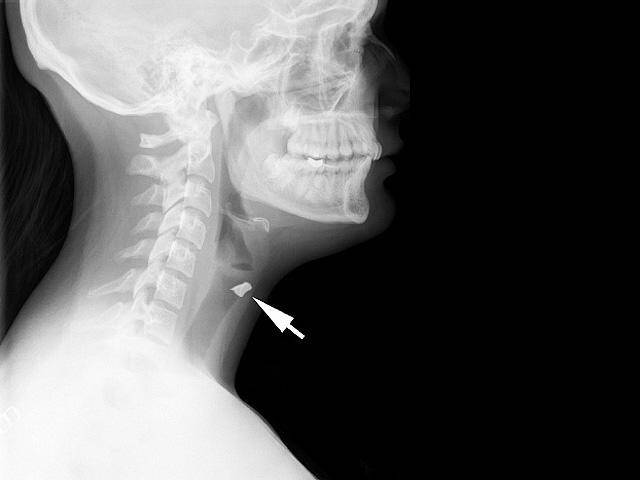

Niektórym osobom, zwłaszcza w wieku nastoletnim, trudno jest się powstrzymać od umieszczania rzeczy pod swoją skórą. Lekarze twierdzą, że rośnie liczba nastolatków – zwłaszcza z depresją lub lękami – które wbijają igły, zszywki, spinacze oraz inne przedmioty pod skórę swojego ciała. Tę dość bezkrwawą praktykę lekarze nazywają czasem “zachowaniem samo-osadzającym” lub “zagnieżdżającym”.

– Okres dojrzewania może być niezwykle stresujący – powiedział dla CBS News dr William E. Shiels, szef radiologii w Nationwide Children’s Hospital w Colombus (Ohio). Jest on autorem nowego badania na temat zachowań zagnieżdżania w sobie przedmiotów, które zostało opublikowane w czasopiśmie Pediatrics. – Dzieci mówią nam, że ból fizyczny jest łatwiejszy do zniesienia niż ból emocjonalny. Umieszczenie w sobie jakiś obiektów odwraca ich uwagę od bólu psychicznego.

Samookaleczenia są niebezpieczne – oprócz ryzyka wywołania infekcji, umieszczanie w ciele przedmiotów może uszkodzić nerwy lub naczynia krwionośne. – W skrajnych przypadkach oprócz krwawienia (w tym wewnętrznego) może wystąpić nawet udar – powiedział Shiels.

– Jeśli dasz niektórym z tych dzieciaków magazyn do poczytania, to odzyskasz go z brakującymi zszywkami – mówi Shils. – Daj im ołówek, a wyciągną grafit i wsadzą do pod skórę.